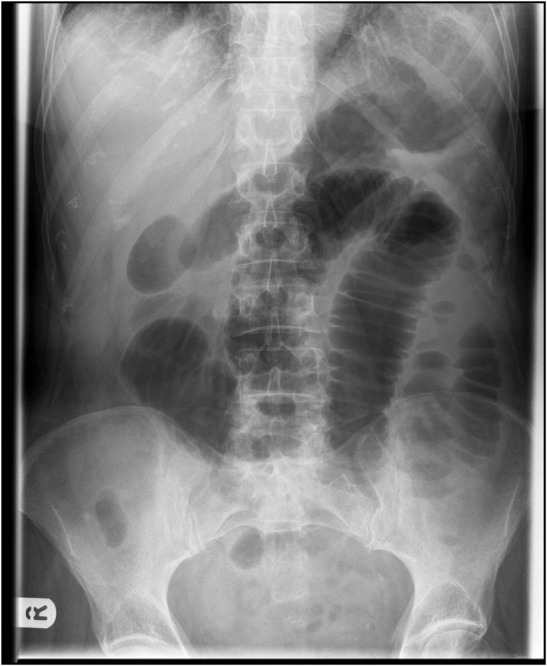

Intestinal obstruction is a common surgical emergency. It has many causes, which may be either benign or malignant. However, appendicitis is not a common cause of intestinal obstruction, hence the challenge in making a diagnosis. Radiological and clinical diagnoses of this could be difficult; hence, diagnosis is mostly intraoperative. This case study involved a 54-year-old male, who presented at Edward Francis Small Teaching Hospital with features of acute intestinal obstruction for 5 days. During surgery, a gangrene of a loop of the bowel was found with an inflamed and partly gangrenous appendix, forming a tourniquet around the loop of the bowel. Appendicectomy and resection of the gangrenous bowel were performed. The postoperative period was uneventful. The patient was discharged on postoperative day 12. We publish this case report to add to the existing literature. In addition, no such case has been reported in the subregion. Appendicitis is not common in the age group in our case study, which makes it different from other cases presented in literature.